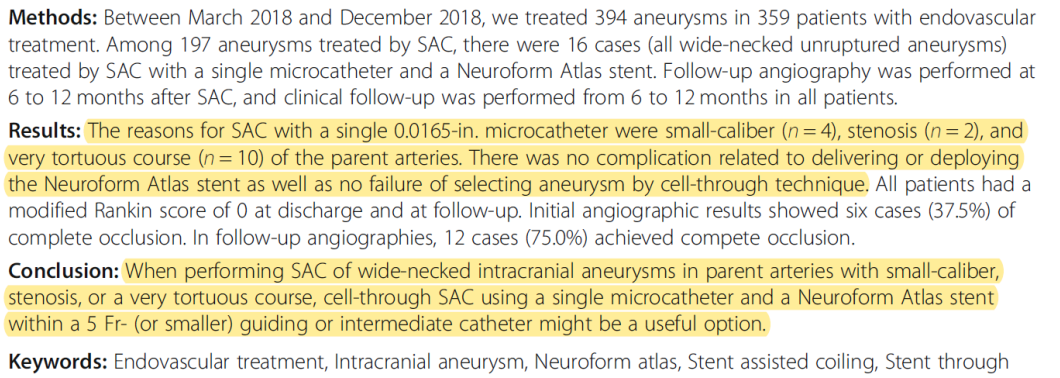

对于以往难处理的未破裂宽颈动脉瘤:

✔载瘤动脉细小

✔伴随近端狭窄

✔路径十分迂曲

Atlas穿网孔技术成功率100%,术后完全闭塞率高。

Atlas支架单系统(5F guider或者中间导管),是实用的选择。